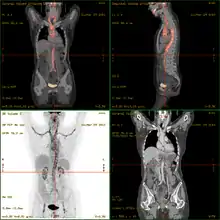

- أصبح التصوير المقطعي بالإصدار البوزيتروني / التصوير المقطعي المحوسب أداة تصوير مستخدمة على نطاق واسع في المرضى الذين يشتبه في أنهم يعانون من التهاب الأوعية الدموية الكبيرة، وذلك بسبب استقلاب الجلوكوز المعزز لجدران الأوعية الملتهبة.[10][11]